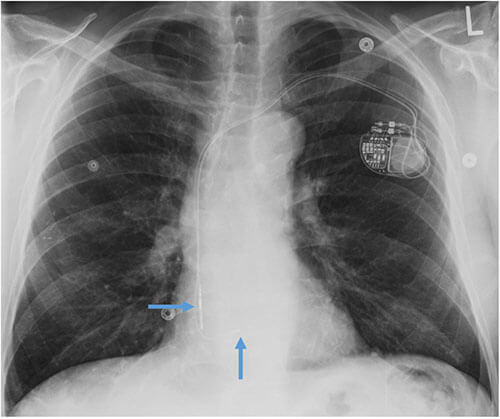

- CEID images with lead types:

Pacemaker with transvenous leads

Pacemaker with epicardial leads

Defibrillator lead

Subcutaneous defibrillator

Cut epicardial wires (often hard to see)

Abandoned leads

Abanded leads plus generator

Temporary transvenous lead

Leadless pacemaker

Abandoned, in situ intracardiac and epicardial leads